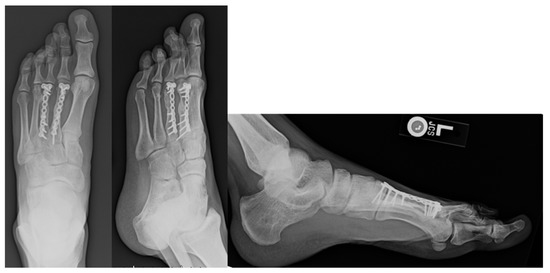

Figure 2.

Post-operative Images for Displaced Non-union. Displayed above are the radiographs for second and third metatarsal fractures following a gunshot injury that underwent ORIF due to a non-union.

Ten fractures received operative management at initial evaluation. Of the 10 operatively treated fractures, 4 were classified as open fractures (Table 1). Three of the open fractures underwent operative fixation primarily. One open fracture was treated non-operatively but required delayed fixation due to non-union. (Figure 1 and Figure 2) One operative fracture underwent revision surgery for a non-union with a 10% reoperation rate. Five were treated with k-wire pinning. Five were treated with open reduction and internal fixation.

If only those patients with greater than 4 mm of displacement were considered operative candidates based upon guidelines, 5 fractures would have met criteria for surgery. Four of those 5 cases were actually treated with an operation at the time of injury. The one case that was initially treated non-operatively later developed a non-union and underwent a non-union repair. It should be noted that the fracture which developed a non-union in this grouping was secondary to gunshot injury to the foot (Figure 1 and Figure 2). The patient who developed a non-union was unable to return to run at final follow-up. Of the 4 patients initially treated operatively, 1 was unable to return to running secondary to pain at the fracture site.